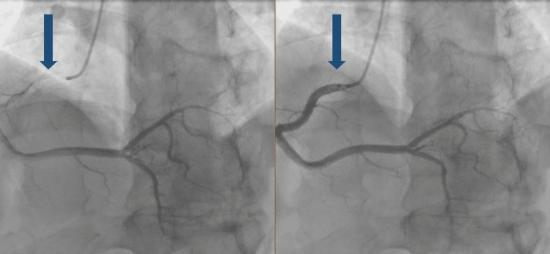

为明确心肌缺血的根本原因,医生们决定进行冠状动脉造影检查

(图2)。造影结果显示:左冠状动脉主干、左旋支及右冠状动脉未见明显狭窄或斑块形成;左前降支中段可见一段血管走行于心肌组织内,心肌收缩期血管管腔明显狭窄(狭窄程度约70%),舒张期狭窄缓解,符合“心肌桥”典型影像学表现。

图2 冠状动脉造影示“挤奶”